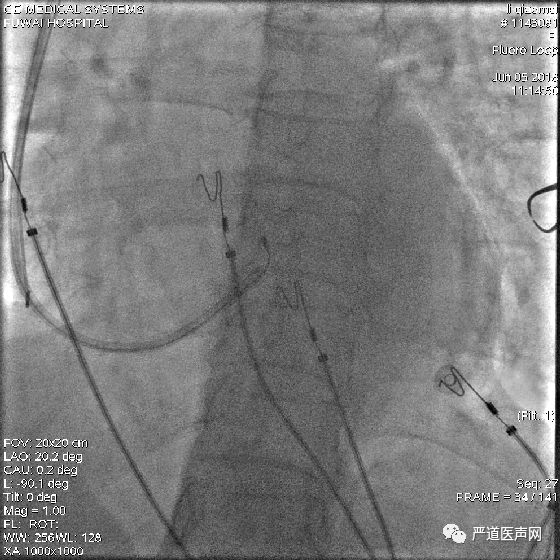

鞘中鞘经泥鳅导丝,通过瓣膜部位

鞘中鞘搭在靶静脉口

经鞘中鞘送左室导线进入侧静脉,张力大,左室导线前行困难

鞘中鞘前行支撑下仍无法进入

将鞘中鞘被再次送到靶静脉口支撑,由于分支太细,左室导线仍无法深入

调整左室导线,进入另一位置较高的分支

再次尝试PTCA导丝进入较高分支,左室导线顺利进入

最终影像

AP

LAO

RAO